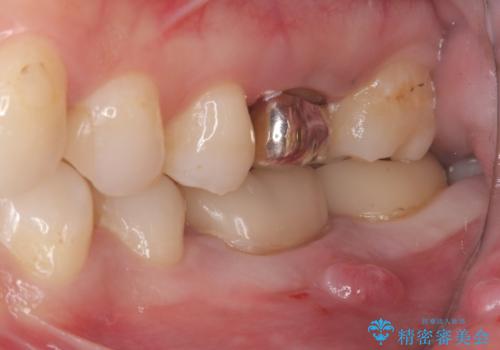

- 主訴:左下6番目の歯の周りが痛くなり、他院で診てもらったが抜歯と言われてしまった。ネットで歯牙移植というものを知りやっている医院を探している。

左下6番目の歯の周りに大きく透過像を認め、再根管治療後の予後が良くない可能性が大きく当院でも抜歯適用歯と説明しました。欠損部に対しインプラント治療や歯牙移植(左下の親知らずの移植)、ブリッジを提案し、歯牙移植を行うこととなりました。

保存が難しい左下6番目の歯を抜歯し、左下8番目の歯(親知らず)を抜歯窩に移植しました。歯牙移植後の動揺防止のため暫間固定を行っています。